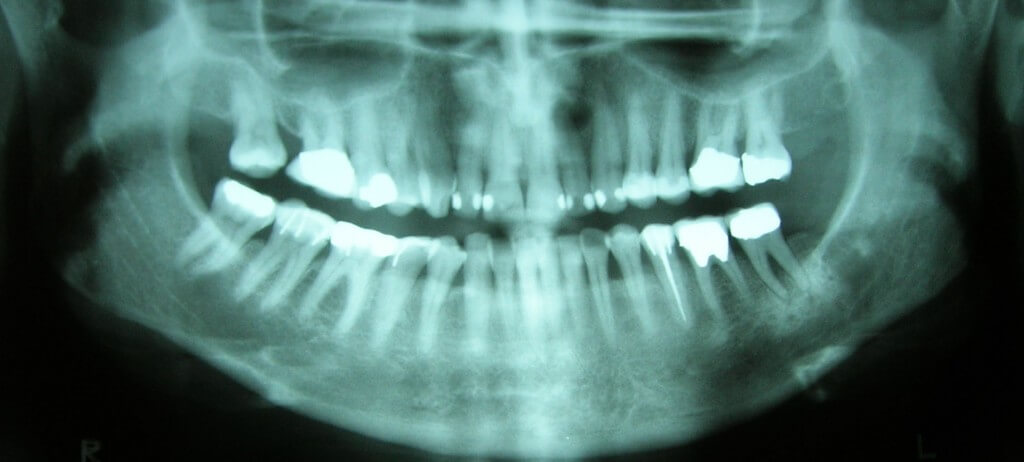

Oral Cancer: Do You Know The Risk Factors?

April is Oral Cancer Awareness Month. We want you to learn the basics so you can reduce your risk.